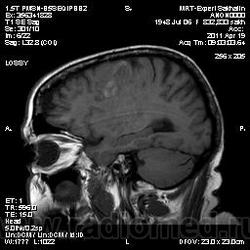

склоняюсь к кровизлиянию в левой теменной долей, начало перехода острой стадии в раннюю подострую( по периферии определяется повышение МРС по Т1 ВИ -метгемоглобин). Справа -старые кортикальные постишемческие глиозно-атрофические изменения. Контрастируется , вероятно за счет формирования участков ангионеогенза.

Это демиелинизирующий процесс, острая стадия, причем с геморрагическим пропитыванием в центре пораженных участков. В принципе, соответствует тяжелому рассеяному склерозу, хотя может быть и геморрагическая форма ОДЭМ. Также могут быть мозговые проявления системного васкулита: надо знать анамнез.

На фоне ДЭП изменений МР-картина ОНМК по ишемическому типу в бассейне ЛСМА с участками геморрагического пропитывания. Аналогичный участок но в более поздней фазе в задних конвнкситальных отделах правой теменной доли.

О.С., я согласен, что контрастирование нехарактерно для ОНМК, ведь в подострую стадию инфаркта наблюдается, как правило, гиральный тип усиления. Плюс, на ОНМК непохоже то, что поражено почти только белое вещество, а кора интактна. И потом, при такой локализации инфаркта обязательно должна быть яркая клиника, и уж никак не только "головная боль".

Что касается снимочков мне кажется что зона патологического сигнала в левой гемисфере можно расценить как подострую стадию ОНМК с геморрагическим пропитыванием, справа как последствия ОНМК. При чем множественные очаги скорей всего как проявление ХМНК. И обязательно рекомендовать контрольное МРТ в динамике . Если это действительно ОНМК на фоне лечения отек уйдет и будет формированиться зона кистозно-глиозных изменений, а если отек будет нарастать значит надо думать о объемном процессе.

ОНМК по геморрагическому типу, почти классика.